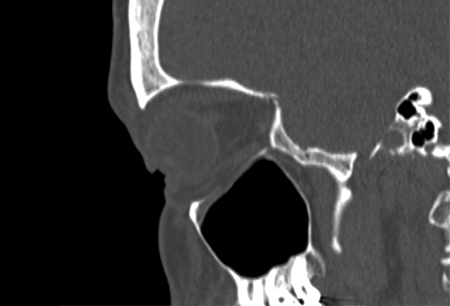

Fine-cut spiral CT with coronal and sagittal reconstructions. [Figure caption and citation for the preceding image starts]: Right orbital blow-out fracture on CT-scan; coronal reformatFrom the personal collection of Dr Alistair Cobb [Citation ends].

[Figure caption and citation for the preceding image starts]: Right orbital blow-out fracture on CT-scan; sagittal reformatFrom the personal collection of Dr Alistair Cobb [Citation ends].

[Figure caption and citation for the preceding image starts]: No evidence of fracture on the left orbit as seen on CT-scan; sagittal reconstructionFrom the personal collection of Dr Alistair Cobb [Citation ends].